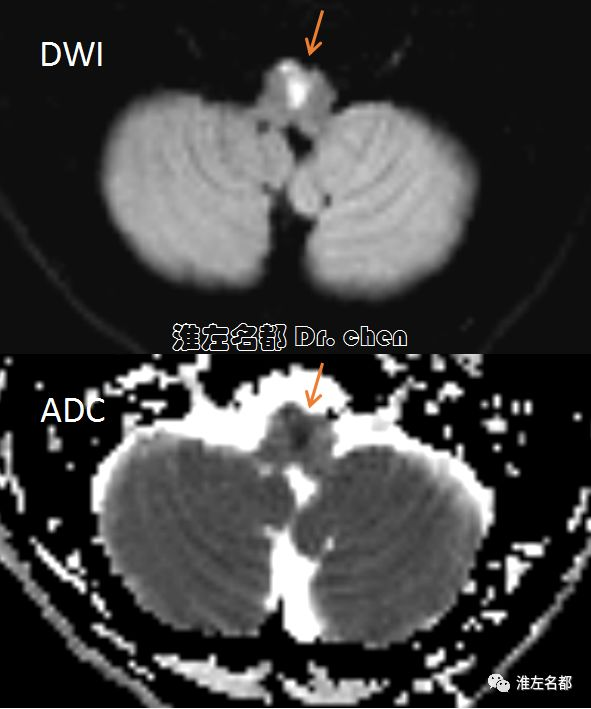

△DWI和ADC:双侧延髓前正中急性梗死(橙箭)。